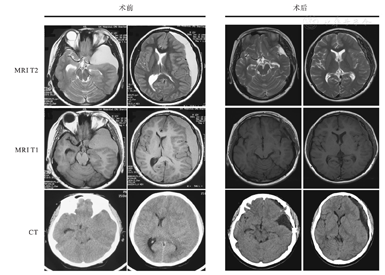

50例患儿术后6个月内原有症状有不同程度改善。所有患儿出院前及术后6个月均复查头部CT,所有患儿侧裂池低密度影范围均较术前有不同程度的缩小。囊肿消失者30例,囊肿仍然存在者20例(其中囊肿明显缩小16例,囊肿略有缩小4例)。术后判定囊肿缩小的指标:(1)囊肿基本消失;(2)囊肿明显缩小(囊肿缩小30%以上,图1);(3)囊肿略有缩小(囊肿缩小10%~30%)。无患儿出现再发硬膜下血肿。

患儿,男,13岁,以头痛2周加重3 d伴呕吐为主诉入院,查体未见神经系统阳性体征。术前CT示左侧颞极、硬膜下等密度新月形占位性病变。MRI T1及T2加权像示左侧颞极、硬膜下稍长T1、稍长T2信号病变,占位效应明显,左侧侧脑室受压,中线结构右移。患儿诊断为左侧颞极蛛网膜囊肿伴硬膜下血肿,于全身麻醉下行开颅显微囊肿切除,血肿清除,脑池沟通术。术后10 d CT示血肿完全清除。术后6个月MRI示蛛网膜囊肿明显缩小。